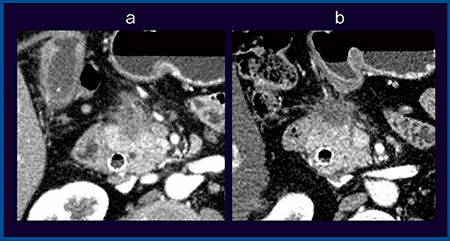

●症例4:肝門部領域胆管がん,術前評価

図5は,60歳代,男性の肝門部領域胆管がんである。正常胆管が描出されており,腫瘍部には微細な浸潤が確認でき,左優位に腫瘍が存在していることがわかる。このような場合,左肝動脈(LHA)と右肝動脈(RHA)の浸潤によって術式を選択し,場合によっては切除の可否も考える必要がある。本症例では,LHAは最大270°程度浸潤があり,encasementはないが浸潤している可能性が高い。一方,RHAも一部が腫瘍に接しているものの,最大でも90°程度であることから,左側を切除し,右側は血行再建術をスタンバイしつつ切除することとして,拡大肝左葉切除・肝外胆管切除術を施行した。進展範囲は術前の評価どおりで,RHAへの浸潤は認められなかった。

図5 症例4:肝門部領域胆管がん,術前評価(60歳代,男性)